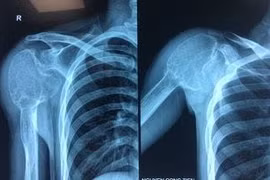

(khoahocdoisong.vn) - Các bác sĩ Trung tâm Chấn thương chỉnh hình và Y học thể thao Vinmec đã thực hiện thành công ca phẫu thuật phức tạp cắt khối nang xương phình mạch có kích thước lớn phá vỡ hết cấu trúc xương đầu trên xương cánh tay phải và thay toàn bộ phần xương cánh tay khuyết hổng bằng kỹ thuật thay khớp vai đảo ngược.

(khoahocdoisong.vn) - Giống như chỉ định chung của các phẫu thuật thay khớp, phẫu thuật thay khớp vai được cân nhắc tiến hành khi khớp bị hư hỏng nặng, ảnh hưởng đến khả năng vận động thực hiện động tác và gây phiền toái cho bệnh nhân trong cuộc sống.